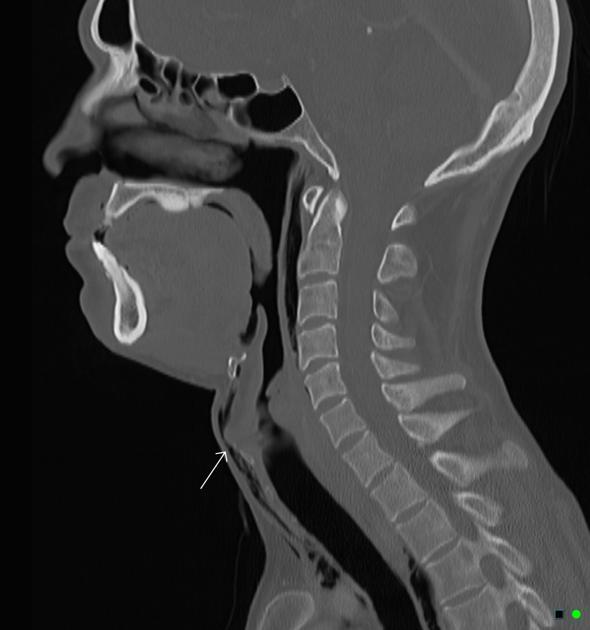

Qual a técnica padrão ouro para estabilização da coluna cervical?

Colar cervical e prancha rígida

Qual a indicação de traqueostomia no trauma?

FRATURA DE LARINGE

Obs: Segundo ultimo ATLS, podemos fazer uma tentativa de IOT antes de partir para a traqueostomia